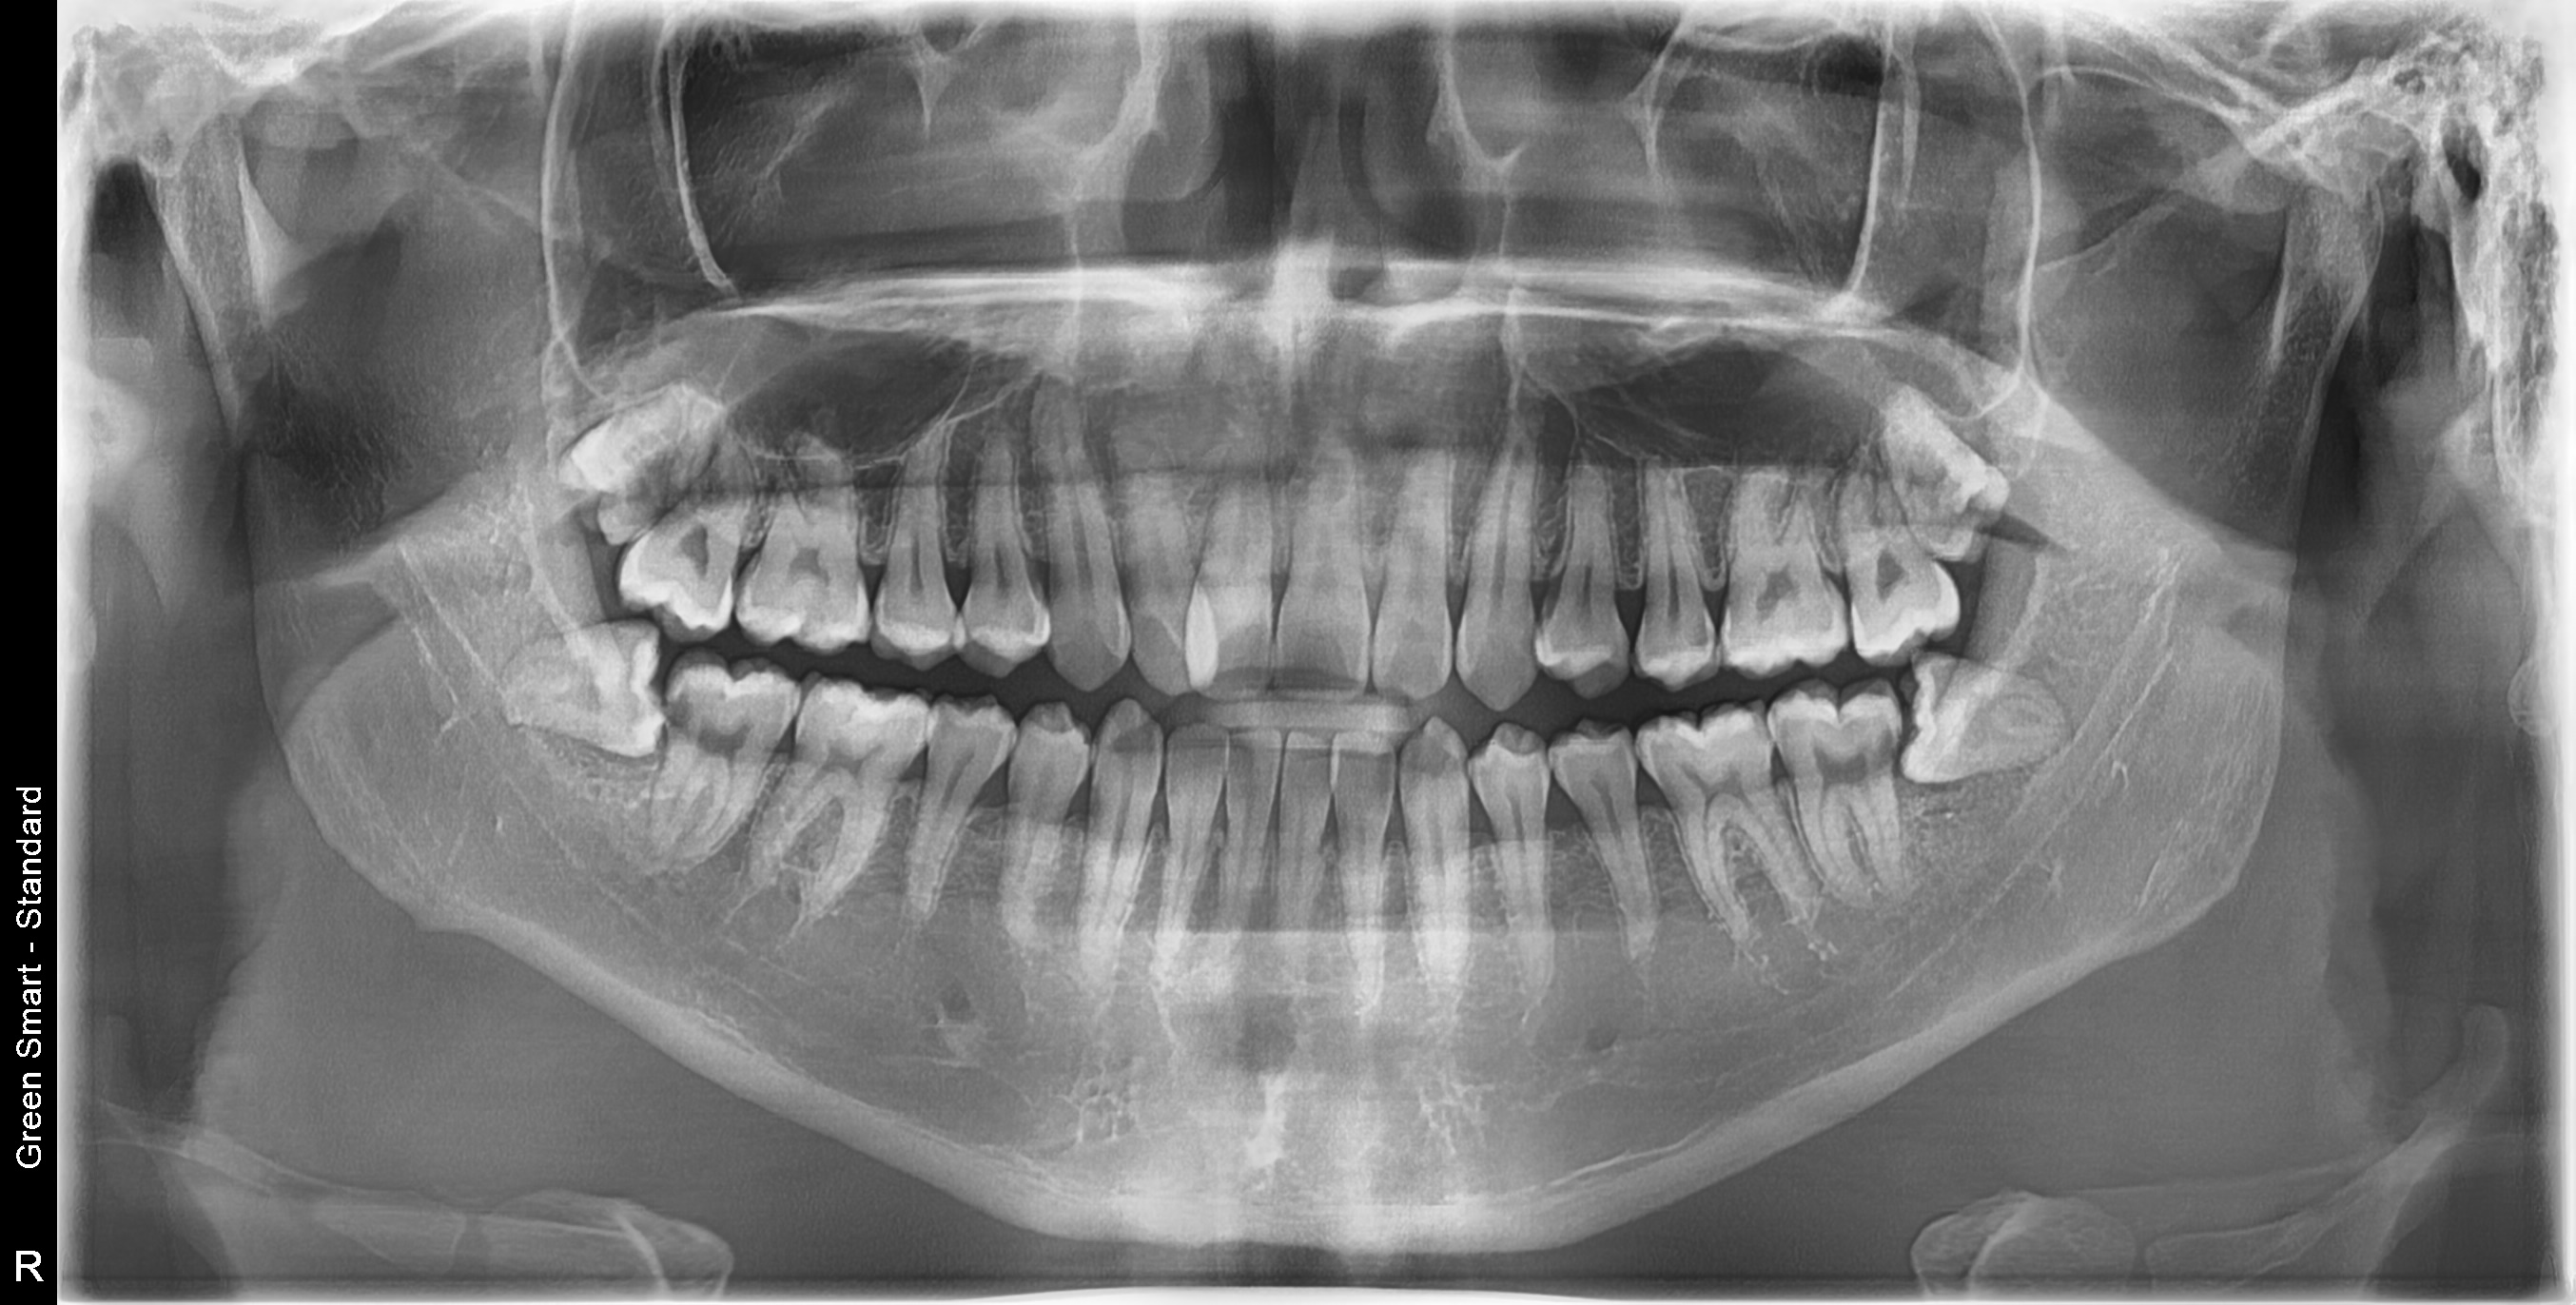

누운 사랑니

옆으로 누워 자라며 옆 치아를 압박할 수 있습니다

중위험

부분매복 사랑니

음식물이 끼기 쉽고 염증이 자주 발생합니다

즉시 처치 필요

수평매복 사랑니

앞 치아를 밀어 치열 불균형과 충치를 유발합니다